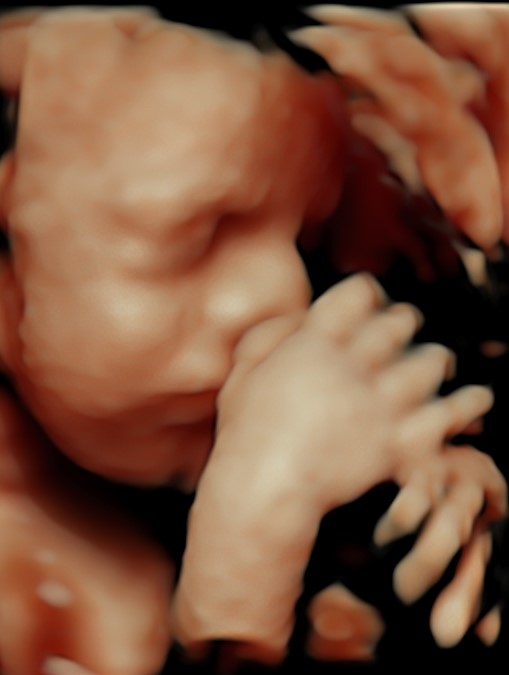

4D/5D/HD Ultrasound Gallery

Gallery